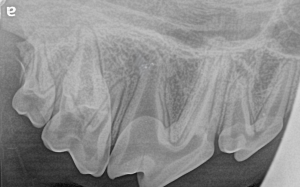

Feline Full Mouth Radiograph example